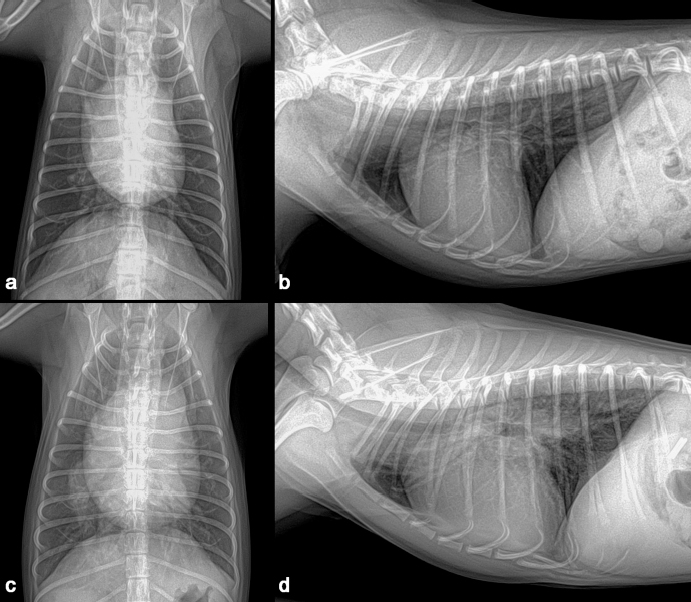

A 1-year-old neutered male Maltese dog weighing 1.4 kg was referred to the Veterinary Teaching Hospital showing microhepatica (Fig. 1a) and hyperammonemia. The dog did not show clinical signs related to portosystemic shunt previously. Although its postprandial ammonia level was in the reference range [18 μmol/l, reference interval (RI): 0–98 μmol/l], hypoalbuminemia (2.1 g/dl, RI: 2.6–3.3 g/dl) and increased levels of serum bile acid (177 μmol/l, RI: 0–25 μmol/l), alanine transaminase (ALT) (254 IU/l, RI: 21–102 IU/l), and alkaline phosphatase (ALP) (1347 IU/l, RI: 29–97 IU/l) were identified. No abnormalities, including cardiac murmur, were observed during physical examination. For a more thorough examination, computed tomography was used, and a CPSS (porto-caval shunt) was diagnosed (Fig. 2a and b). After preoperative medical stabilization, surgery was performed for shunt attenuation. Anesthesia was induced with propofol (8 mg/kg, IV) and maintained by isoflurane. Perioperative pain was managed by tramadol (5 mg/kg, IV). From the xiphoid process to the pubis, a standard ventral midline approach was taken. After dissecting the shunt from surrounding tissues, portal pressure was measured from the jejunal vein. Baseline portal pressure was measured to be approximately 7–8 mmHg (RI: 6–10 mmHg). It increased to 13–14 mmHg after temporary complete occlusion of the shunt. The shunt was attenuated using a cellophane band. The abdominal cavity was closed in a routine manner. Its recovery from anesthesia was uneventful. Postprandial serum bile acid (12 μmol/l), albumin (2.6 g/dl), and ALT (29 IU/l) levels returned to their normal ranges at 1 month after the operation. Its serum ALP level also decreased to 430 IU/l, although it was above the RI. An increase in liver size was observed by abdominal radiographs 1 month after surgery (Fig. 1b). Because the majority of the CPSS anomalies were cured throughout the follow-up period, the dog was able to return to normal life without the need for supporting medicine. One year after surgery, the dog was presented to the Veterinary Teaching Hospital for exercise intolerance. Blood gas analysis revealed hypoxemia (73.6%, RI: 95%–99%). A cardiac murmur was auscultated. When compared with thoracic radiographs evaluated at the time of the operation (Fig. 3a and b), the vertebral heart scale increased from 10 to 11.7, indicating generalized cardiomegaly (Fig. 3c and d). Following echocardiography revealed ASD and pulmonary hypertension (Fig. 4a and b). A bubble study confirmed right-to-left shunt. Surgical or interventional therapy was not contemplated due to the dog's tiny size (1.7 kg) and reversed interatrial shunt. Thus, medical treatment was performed to reduce pulmonary hypertension (sildenafil, 1.5 mg/kg, PO, q12 hours). Hypoxemia was improved (94%) after a month of treatment. The dog's activity intolerance had been overcome, according to the owner. As a response to the medical treatment was generally good, therapy was still maintained without changing medication for the next 16 months after diagnosis of the ASD.

Fig. 1. Preoperative abdominal radiograph revealed microhepatica (a). An increased liver size was seen in abdominal radiograph one month after the operation (b).